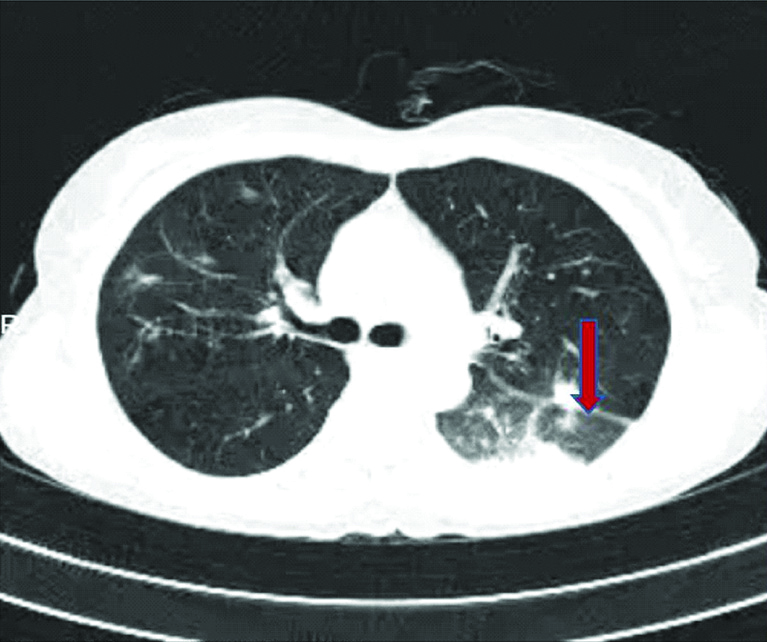

After one-week observation, there was no effect on symptoms of fever, cough, and breathlessness on exertion. Notably, serological examinations revealed positivity for RA factor and anti-Cyclic Citrullinated Peptide antibodies (anti-CCP Abs). Her C-reactive protein was also positive. As there was no response from treatment, High-Resolution Computed Tomography (HRCT) scan of chest was planned which revealed peribronchial and subpleural bilateral ground-glass opacities with air bronchograms. By these findings, possibilities of COP were considered [Table/Fig-1]. Her trans-bronchial lung biopsy examinations couldn’t be performed due to financial and feasibility constraints.

HRCT chest showing peribronchial and subpleural bilateral ground-glass opacities with air bronchograms (arrow).